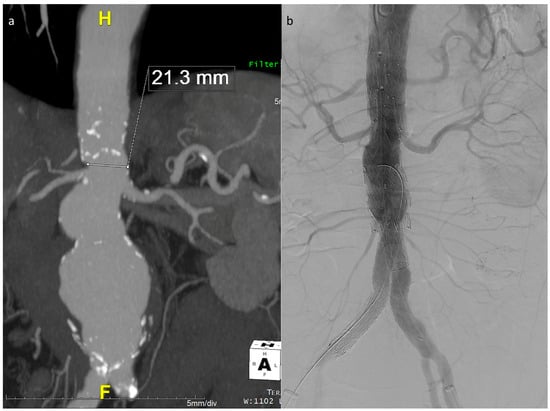

The described technique was used in 26 out of the 40 E-nside cases performed in the two authors’ institutions from January 2020 to March 2024, enabling the treatment of anatomies with an inner aortic lumen down to 20 mm in diameter (Figure 3).

Figure 3. Maximum intensity projection coronal view of the example case in Figure 1, showing a very narrow lumen just above the origin of the renals in a patient with a wide pararenal aneurysm (a). Final angiographic control (b).